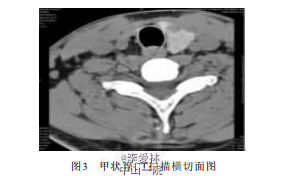

超声所见:于颈部行多切面扫查,气管右侧及前方均未见甲状腺回声(图1),仅于左侧探及甲状腺 回声,大小约2.2ncm×1.7ncm×1.5ncm,边界清晰,实质回声欠均匀,内可见一低回声结节,大小约0.9n cm×0.9n cm(图2)。 超声诊断:①甲状腺先天发育异常(右叶及峡部缺如)。②甲状腺左叶多发结节;后经CT扫描确诊右叶甲状腺及峡部未见(图3)。 ③左叶甲状腺腺瘤。